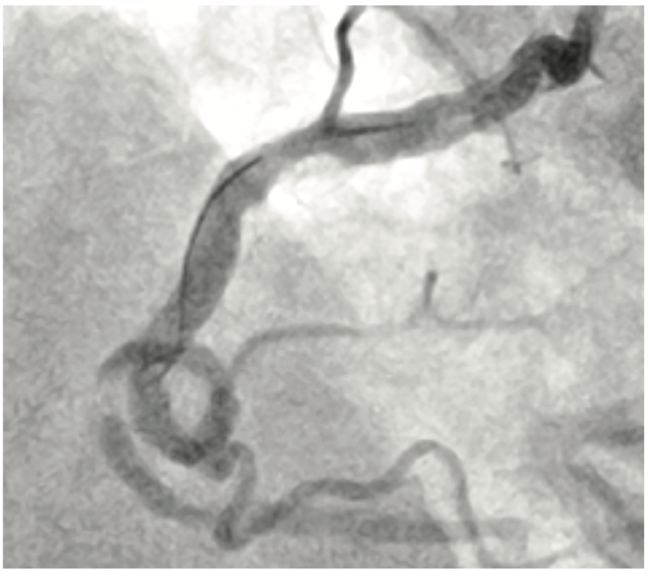

A 70-year-old gentleman presented with Canadian Cardiovascular Society (CCS) class III angina despite two anti-anginals (Metoprolol XL 25 mg daily and ranolazine 500 mg BID). His myocardial perfusion imaging demonstrated medium-sized inferior wall reversible defect with normal left ventricular function. His other comorbidities included chronic atrial fibrillation (on apixaban 5 mg BID), hypertension, and hyperlipidemia (on rosuvastatin 40 mg daily). His angiography revealed severe stenosis of the mid right coronary artery (RCA) involving a 360-degree loop. Further analysis of the angiogram revealed multiple contiguous lesions in the RCA with severe calcific lesions proximal and distal to the loop (Figures 1 and 2). Given severe tortuosity, rotational atherectomy would be challenging and we were hoping to achieve a good result using a balloon catheter strategy.